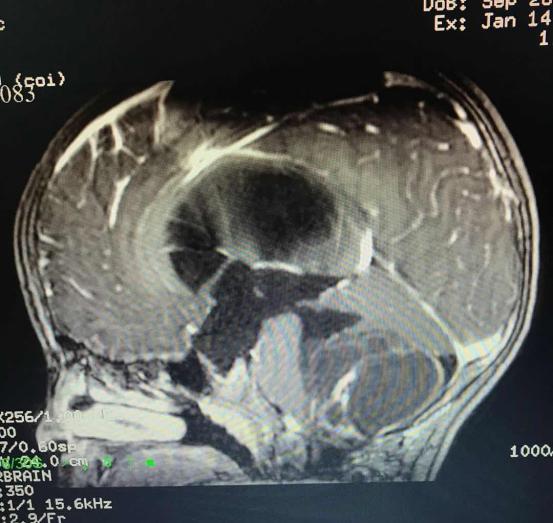

CT显示第四脑室右侧侧孔-桥小脑角区占位性病变,有鸡蛋大小的肿瘤(48mm*38mm*35mm),术后病理证实为毛细胞型星形细胞瘤(WHO1级)。

*术前CT影像资料*